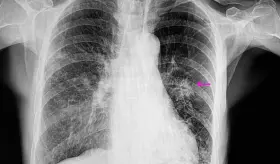

Radiólogo especialista destaca la importancia de la visión independiente del profesional en imágenes diagnósticas para detectar fibrosis pulmonar progresiva y guiar tratamientos específicos según cada patología autoinmune.

Muchas enfermedades pulmonares intersticiales pasan desapercibidas porque sus síntomas imitan a los del asma o la EPOC. Esta confusión retrasa el diagnóstico y pone en riesgo la vida del paciente.